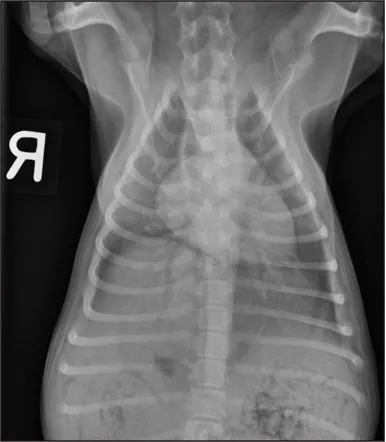

CASE 1.1 A 7-year-old neutered male Labrador Retriever who was hit by a car. You obtain these thoracic radiographs: Figs. 1.1a, b, left and right lateral projections, respectively; Figs. 1.1c, d, ventrodorsal and dorsoventral projections, respectively.

1.1d